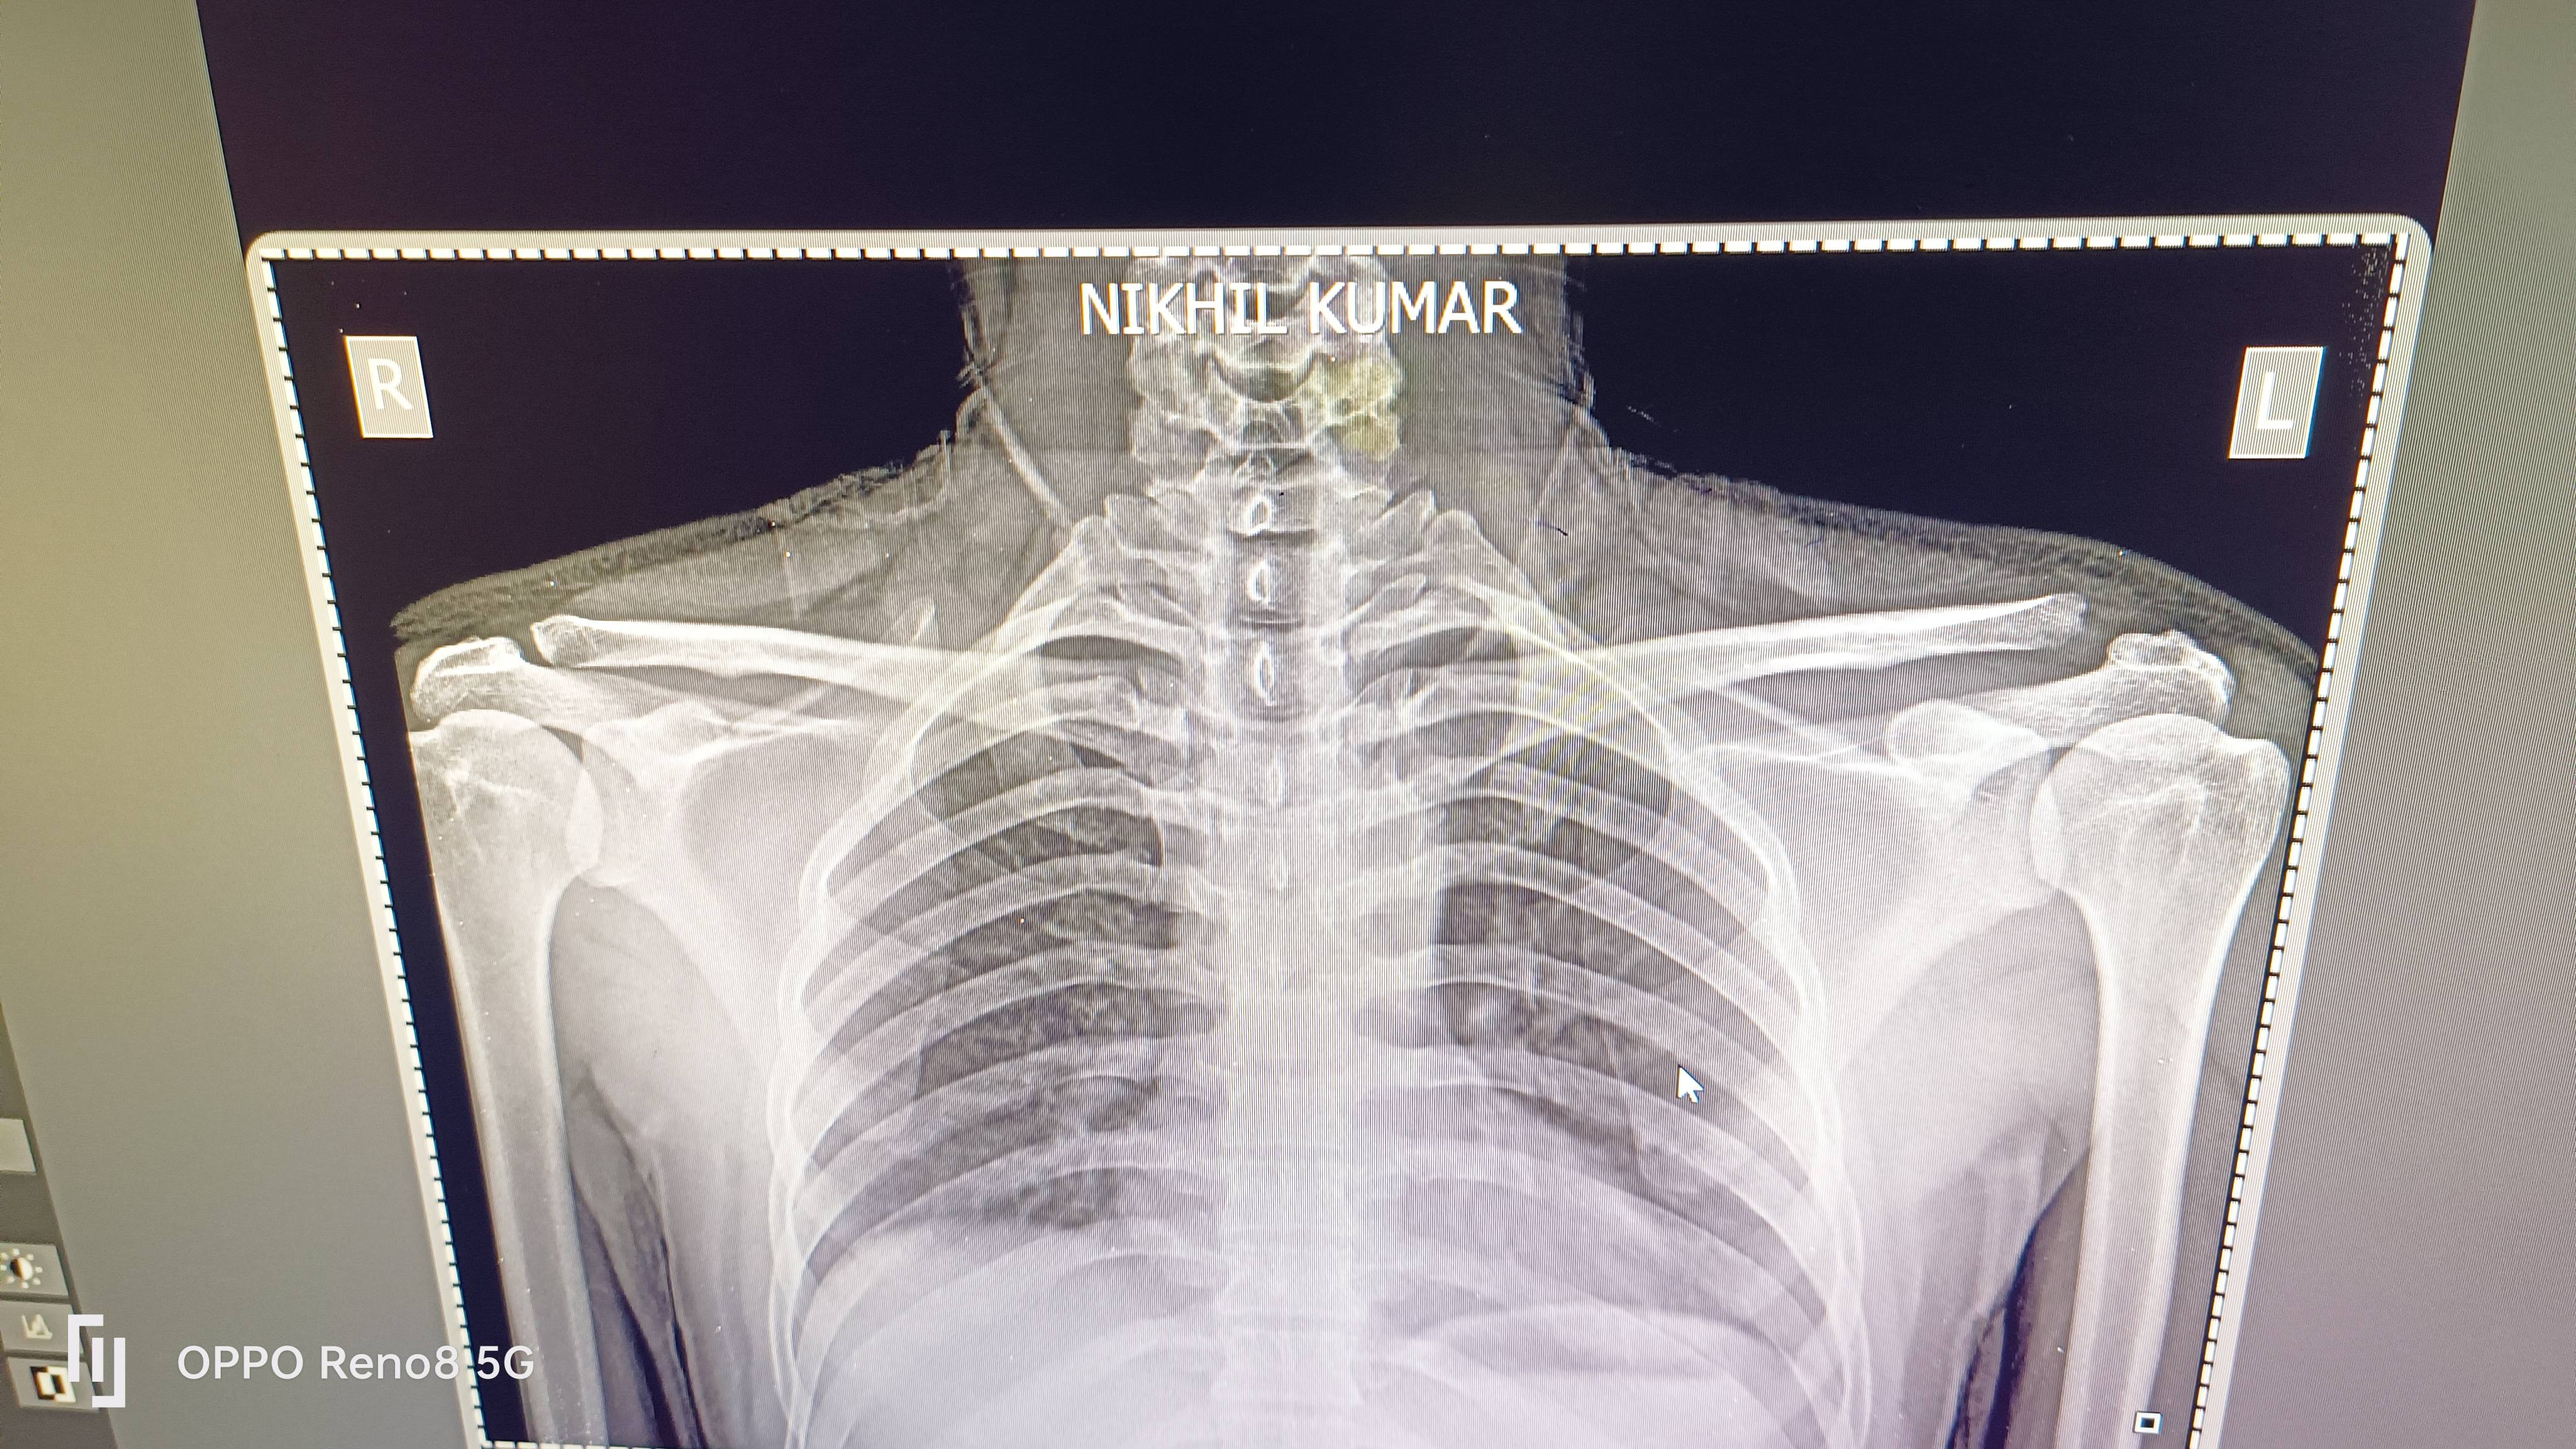

Nikhil kumar